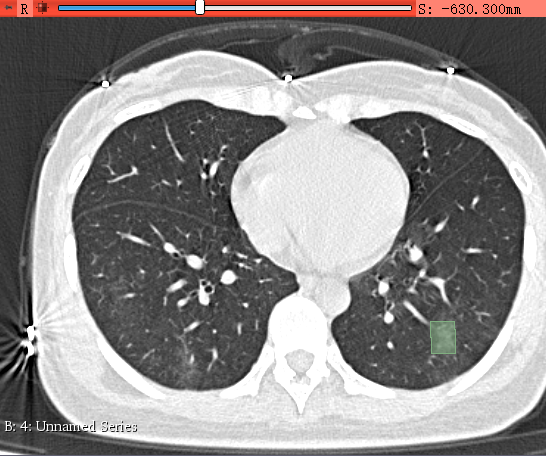

右键生成闭合多边形(伪矩阵):

一个病灶区域就标好了。注意:虽然说在Detection时需要的是矩形框,但是只要所生成的多边形包围着病灶就OK了,后期把多边形转为矩形就行了,即包围多边形的最小矩阵。

标注的要求:病灶区域的多边形,不是矩阵也行,也不需要严格地沿着病灶区域的边界画,把病灶区域给包围住就行,但是尽量不要把非病灶区域给包了。